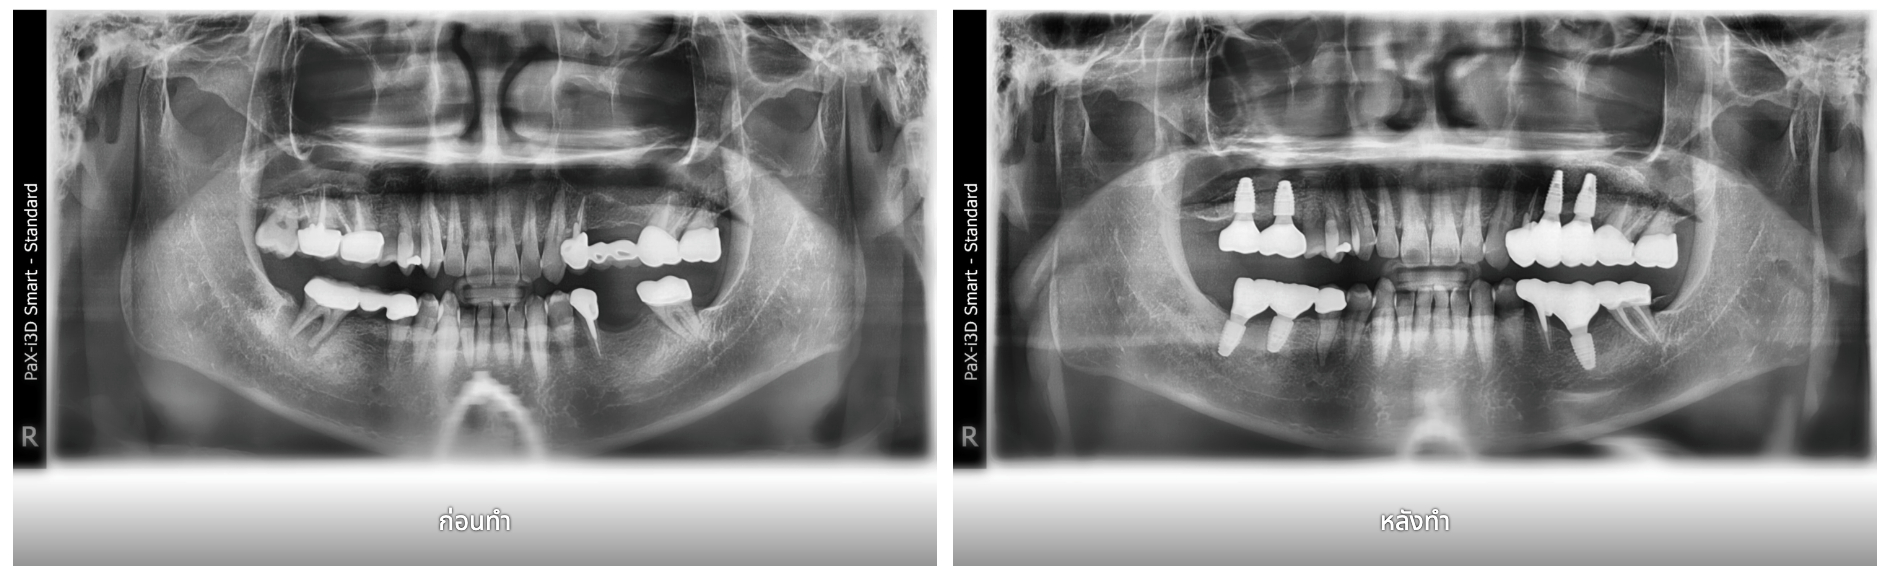

รูปภาพ Belix Dental